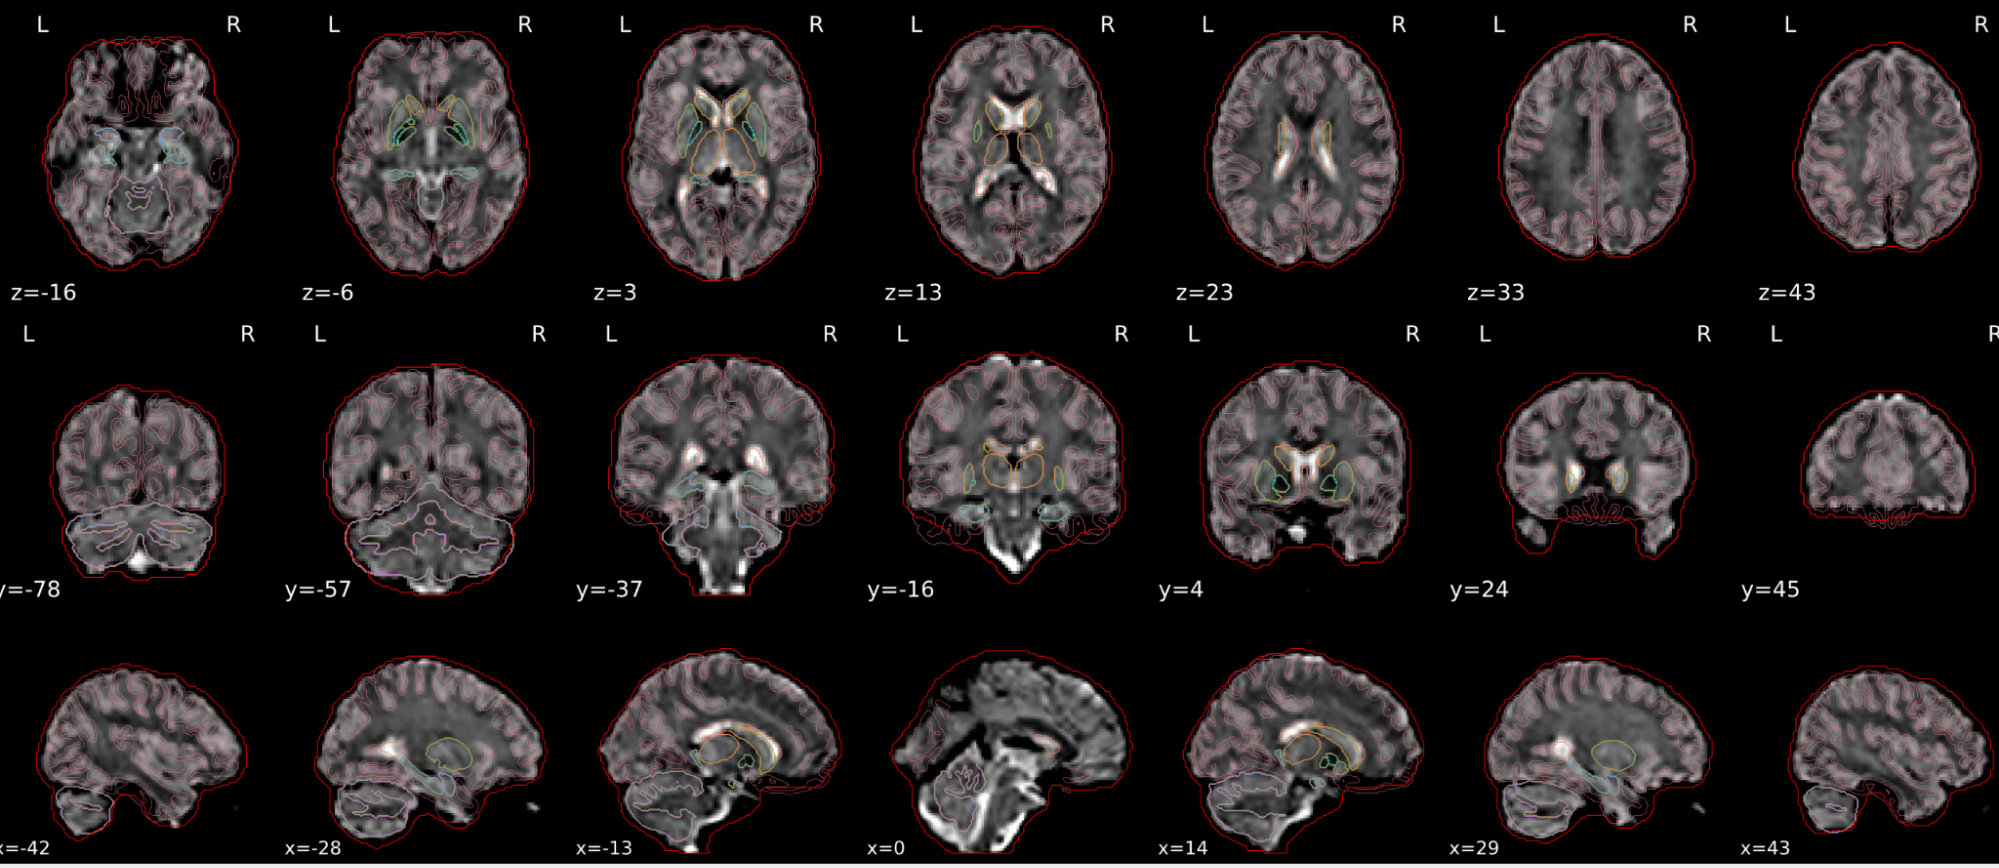

This QC step shows the registration of the T1 image to MNI space.

The registered T1 image is shown in the background with a brain atlas in MNI space as an overlay.

Example of a good subject

- If the registration performed well, you should see an overlap (i.e., correspondence of structures) between the MNI template and the T1 registered to the MNI space.

Example of a bad subject

- In case of poor registration, you should see a misalignment between the MNI template and the T1 (e.g., brain shifted down).

Summary

| good | bad |

|---|---|

| Structures of the MNI template and the registered T1 are well aligned | Structures of the MNI template and the registered T1 aren’t well aligned, e.g. brain is shifted downwards |